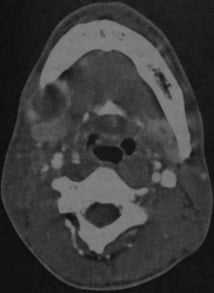

КТ с контрастированием: абсцесс дна полости рта справа с распространением под нижнюю челюсть. Абсцесс примыкает с правой стороны к телу нижней челюсти, определяется как образование со сниженной плотностью в центре, окруженное усиленной стенкой. Поднижнечелюстная железа смещена кзади (стенка абсцесса интактна, инфильтрация в данном случае отсутствует).

Абсцесс дна полости рта, расположенный справа около средней линии. КТ с контрастированием: объемное образование с типичным снижением плотности в центре, окруженное усиленной стенкой. Мелкий абсцесс слева, примыкающий к нервно- сосудистому пучку, с сопутствующим отеком поднижнечелюстных мягких тканей.